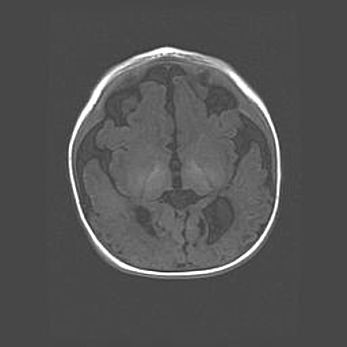

Неполная лизэнцефалия (пахигирия). Открытая гидроцефалия.

Возраст: 17 дней

Вес: 3110 г

Пол: мужской

Окружность головы: 33,5 см

Срок гестации: 35-36 недель

Лизэнцефалия—недоразвитие корковой пластинки и мозговых извилин в результате нарушения миграции нейронов коры. Поверхность мозговых полушарий гладкая. Микроскопически выявляется отсутствие нормальных слоев коры и скопление групп нейронов в подкорковом белом веществе.

Пахигирия—уменьшение числа вторичных извилин. В пораженном полушарии нервные клетки образуют толстый недифференцированный слой с неправильно расположенными нервными волокнами и группами гетеротопных клеток. Нервные клетки незрелые. Белое вещество истончено. При этом нередко аномально развит корково-спинномозговой путь.